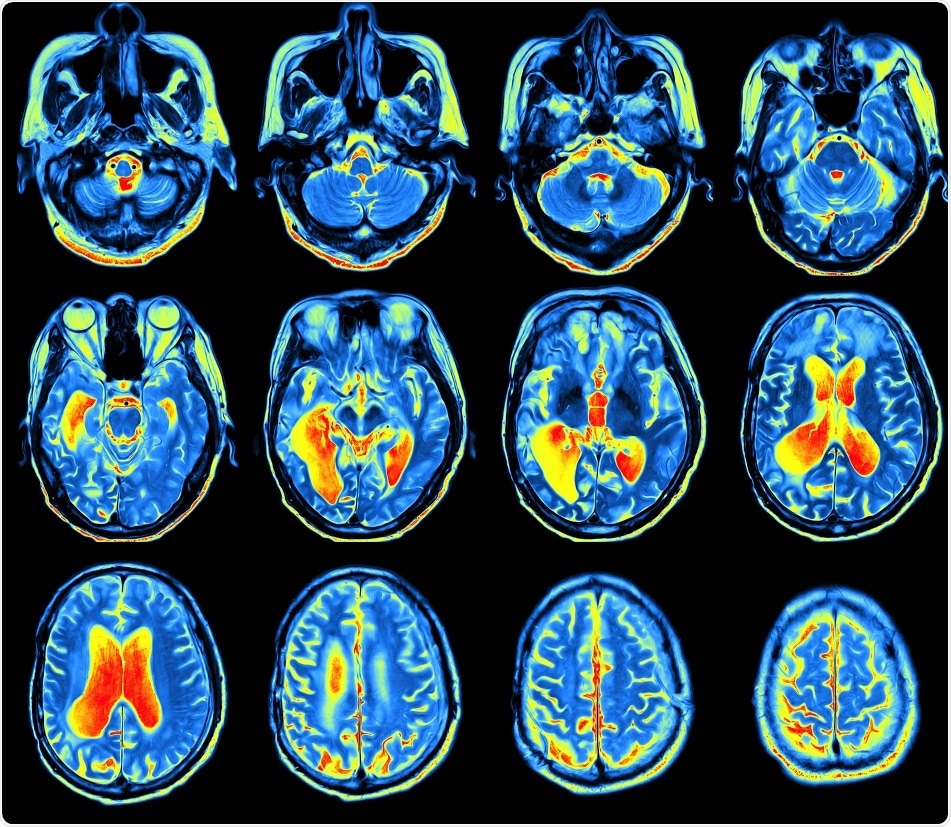

Credit: MriMan/ Shutterstock.com

The study, which was published in the journal Neuron, suggests that it is possible to build up a map of the connectome---the connections in the brain---by examining conventional brain scans obtained using a magnetic resonance imaging (MRI) scanner.